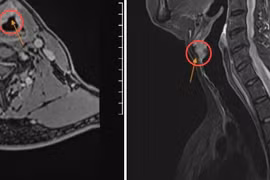

Triệu chứng của ung thư thanh quản (khoahocdoisong.vn) - Ung thư thanh quản là khối u nằm trong lòng thanh quản là loại ung thư hay gặp ở Việt Nam. Đau chỉ xuất hiện khi khối u đã lan rộng, nhất là khi khối u đã bị loét. Đau thường lan lên tai và đau nhói lúc nuốt.